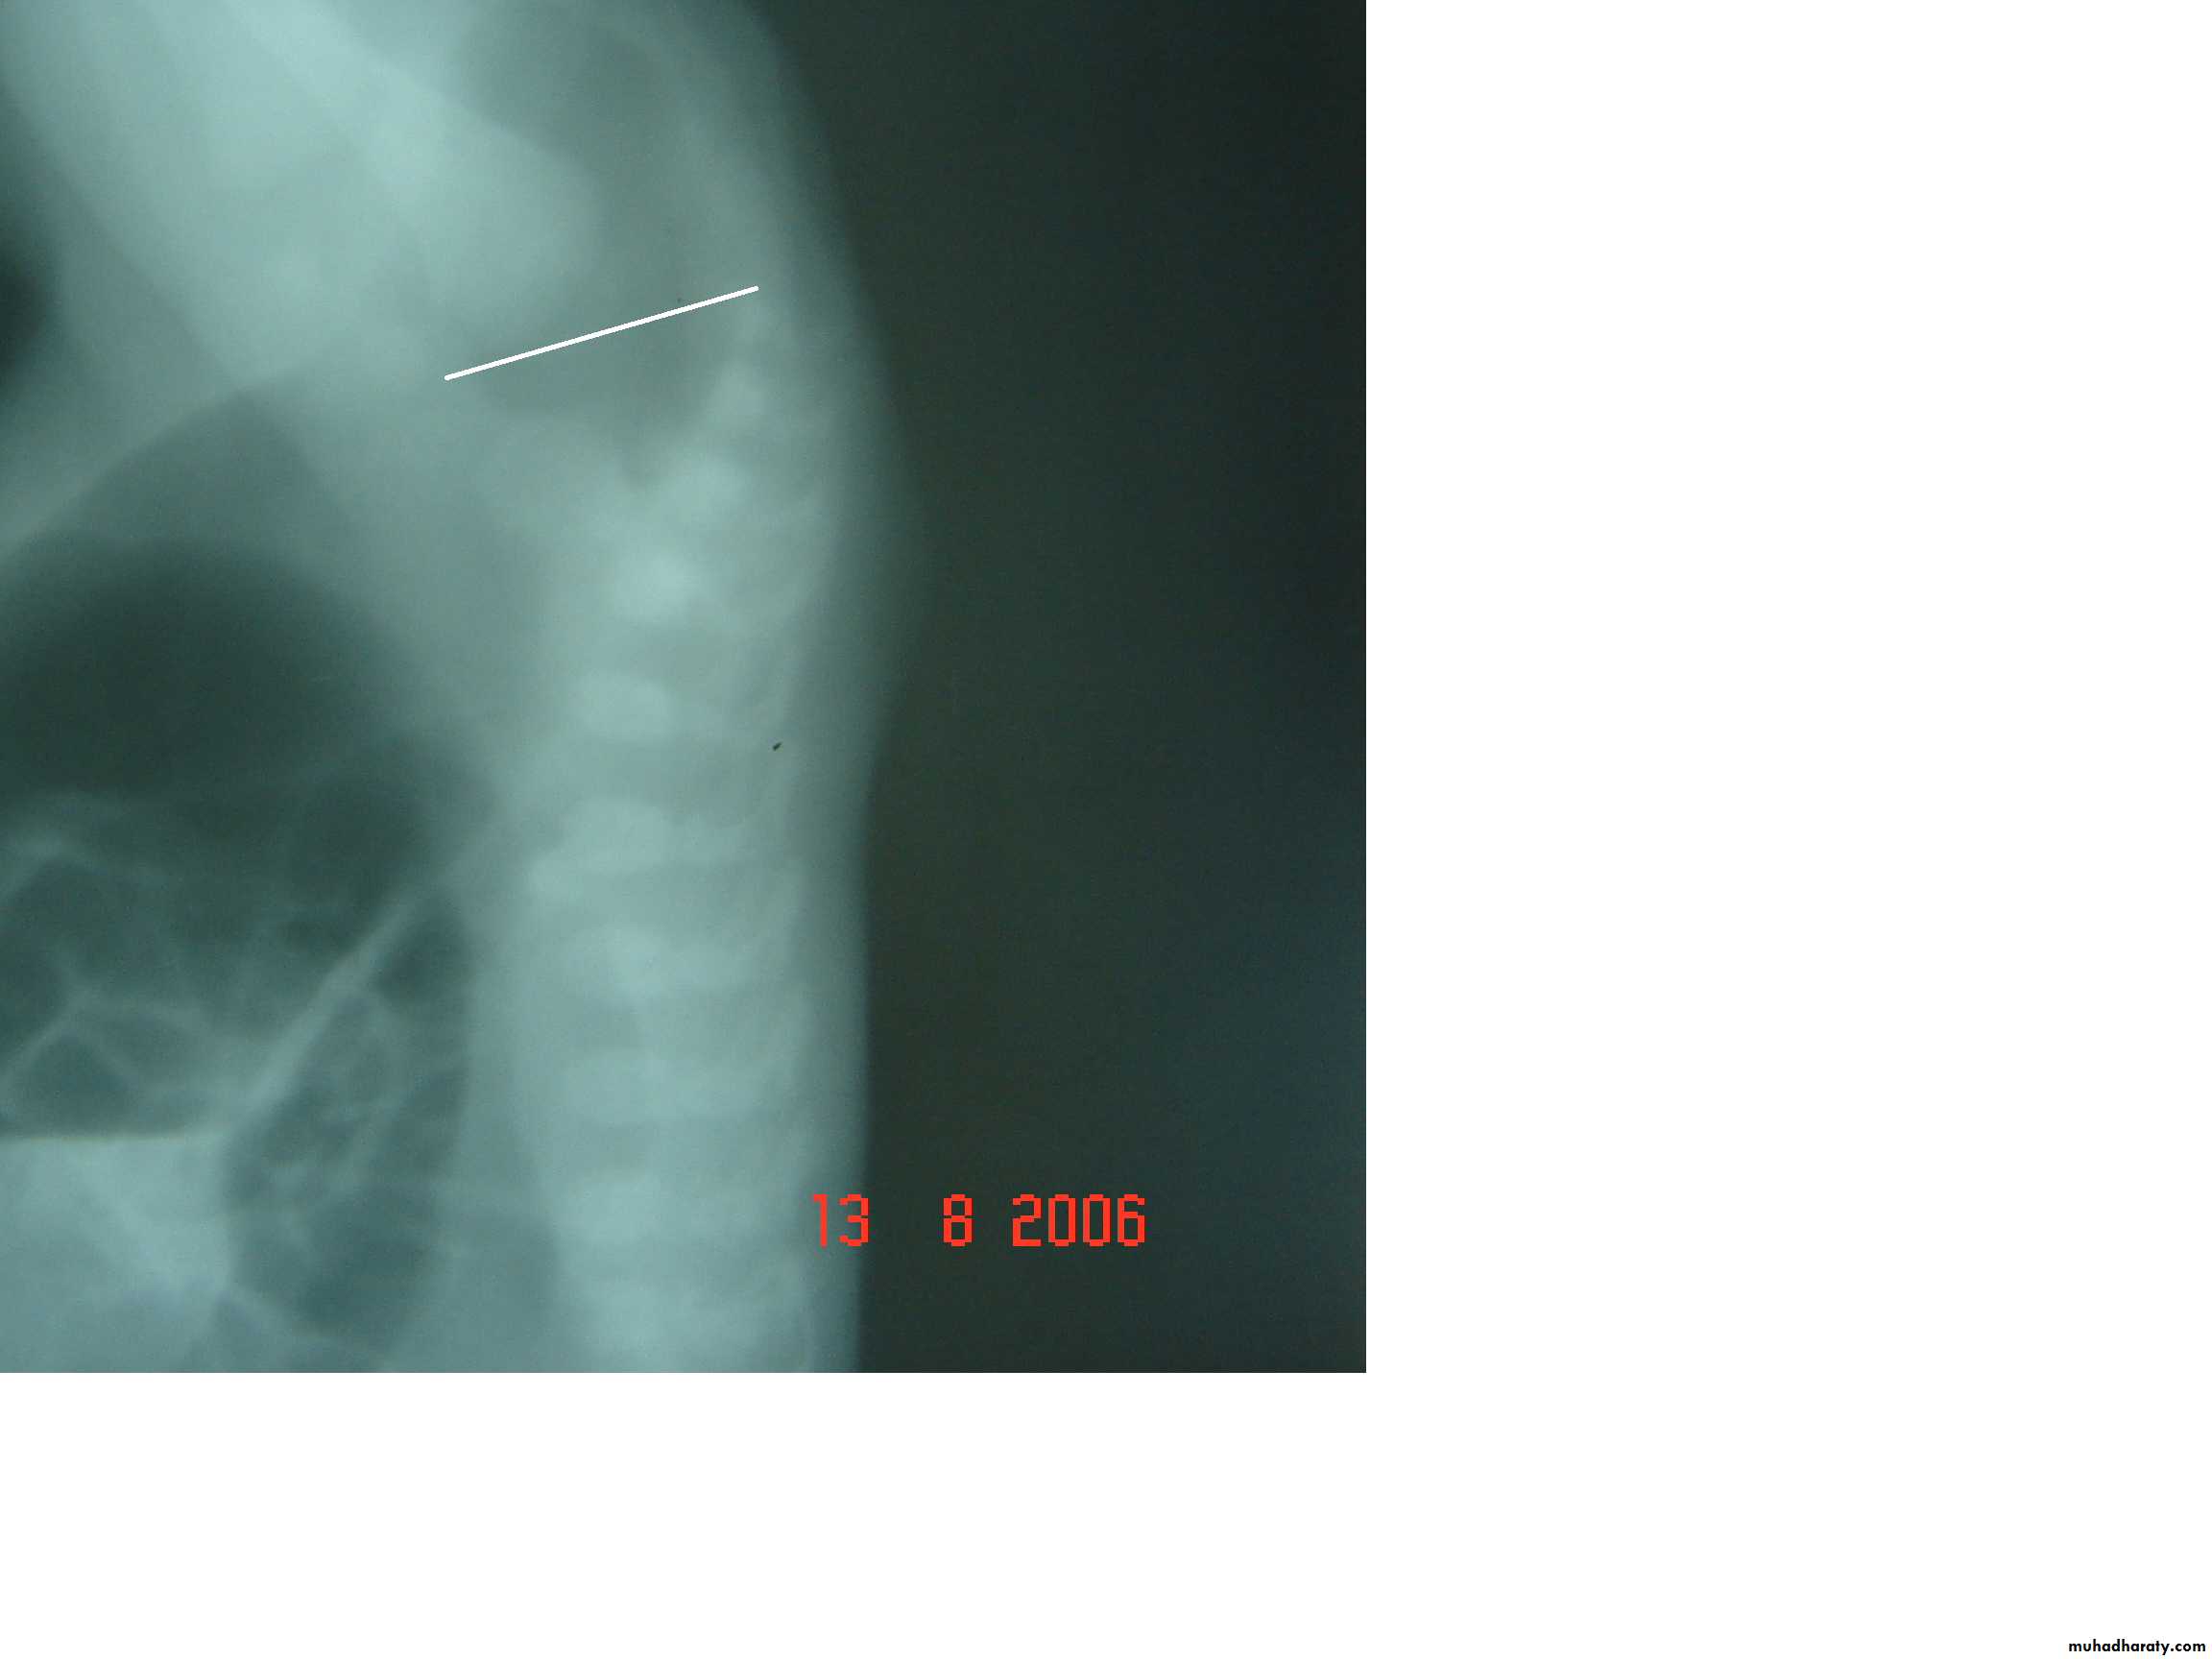

2-Lateral invertogram ( pubococcegeal line) 18-24hr.after birth.

-gas shadow above this line suggest high type.

- gas shadow below suggest low type.

3-lateral decubitus X-ray.